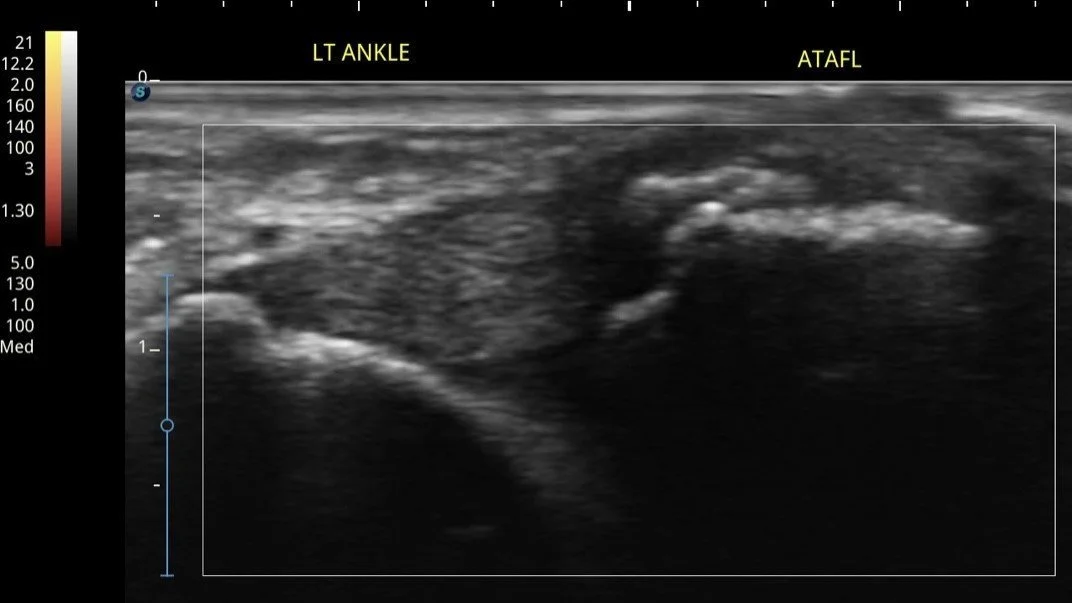

Musculoskeletal Ultrasound evaluates the integrity of the ligaments and tendons as well as assess ankle stability (British Musculoskeletal Disorder 2021). Benefits of Ultrasound over the MRI are clinician can perform dynamic interrogation to check full integrity of tendon and ligaments, very affordable price as compared to MRI, same day appointments and same day result.

Ultrasound: Partial Thickness Tear in TaloFibular Ligament with Bony Irregularity and Swelling in the Ligament following a Sprain Injury